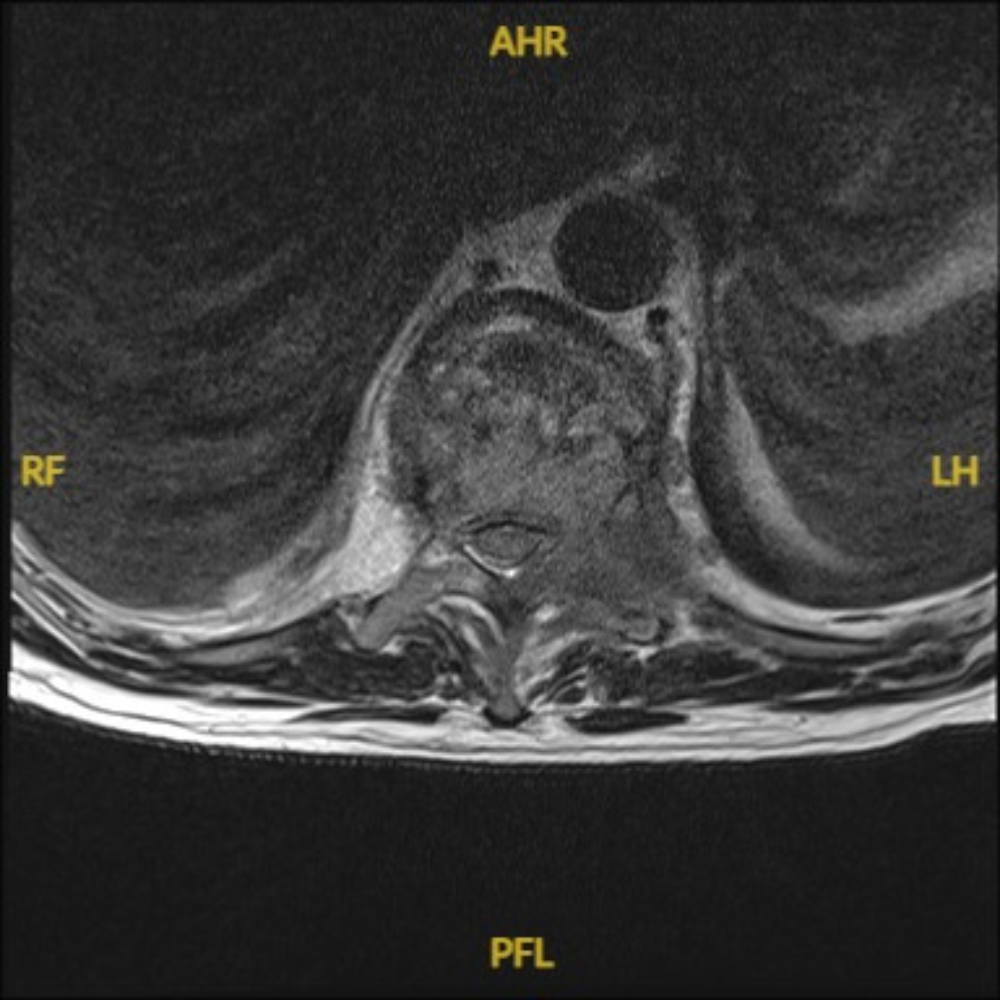

1. Pre-Surgical Evaluation: Includes imaging studies (MRI, CT, or X-rays), biopsy (if needed), and a thorough assessment of overall health.